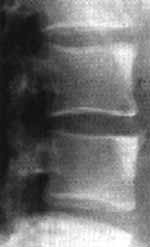

Осссификация передней продольной связки (Рис. 2.), а так же фиброзного кольца сочетается с остеопорозом тел позвонков (в первую очередь губчатой ткани). Иногда может отмечаться столь выраженная деминерализация, что тело позвонка становится даже менее плотным, чем межпозвонковый диск.

Рис. 2. РКТ поясничного отдела позвоночника. Оссификация правой боковой продольной связки и признаки анкилозирования межпозвонковых суставов.